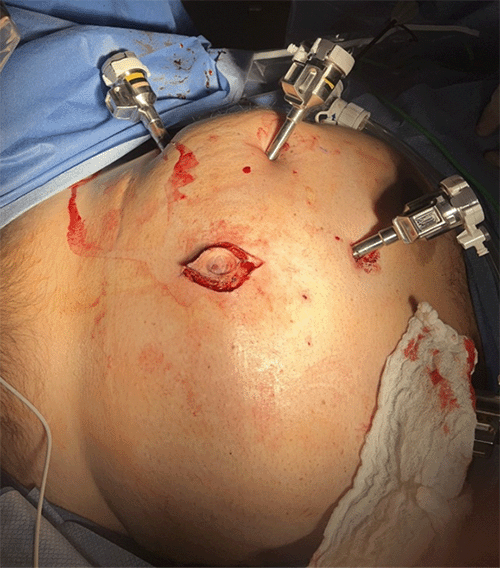

After delineation of the relevant urologic and colorectal anatomy, the sigmoid colon was meticulously mobilized from the dome of the bladder using sharp dissection and judicious electrocautery, and the colo-vesical fistula was sharply transected. Once the colon was fully mobilized away from the bladder and urachal structures, the urology team proceeded with an en-bloc excision of the urachal sinus (Figure 6). A partial cystectomy was performed, excising the dome of the bladder at the site of urachal insertion; this resected bladder segment also encompassed the area involved in the colo-vesical fistula. Following urachal detachment and partial cystectomy, the bladder was reconstructed in multiple layers. The urachal sinus tract, along with its cutaneous fistula, was then excised via an elliptical incision incorporating the umbilicus (Figure 7, Figure 8). Subsequently, the colorectal team performed a robotic-assisted sigmoidectomy with a primary intracorporeal anastomosis. A 19-French Jackson-Pratt drain was placed in the pelvis, and an indwelling Foley catheter was left for bladder drainage to facilitate healing of the cystorrhaphy.

Figure 7. Umbilical Incision for Excision of Cutaneous Fistula. Published with Permission